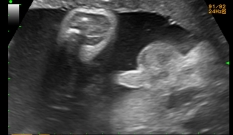

Se você ainda não fez, é hora de agendar o ultrassom do terceiro trimestre, em que se quantifica o líquido amniótico do feto, revisa-se a sua morfologia e se estima seu peso por medidas da cabeça, do abdômen e do fêmur.

| No ultrassom do terceiro trimestre, quantifica-se o líquido amniótico do feto, revisa-se a sua morfologia e seu peso é estimado por medidas da cabeça, do abdômen e do fêmur. |